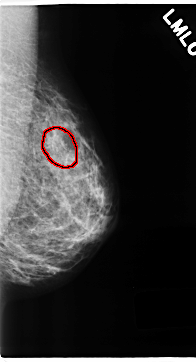

C_0199_1.LEFT_MLO

FILE: C_0199_1.LEFT_MLO.OVERLAY

TOTAL_ABNORMALITIES 1

ABNORMALITY 1

LESION_TYPE CALCIFICATION TYPE PLEOMORPHIC DISTRIBUTION CLUSTERED

ASSESSMENT 5

SUBTLETY 4

PATHOLOGY MALIGNANT

TOTAL_OUTLINES 1

BOUNDARY